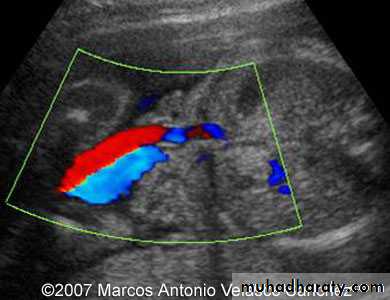

Doppler

Duplex in varicose veins